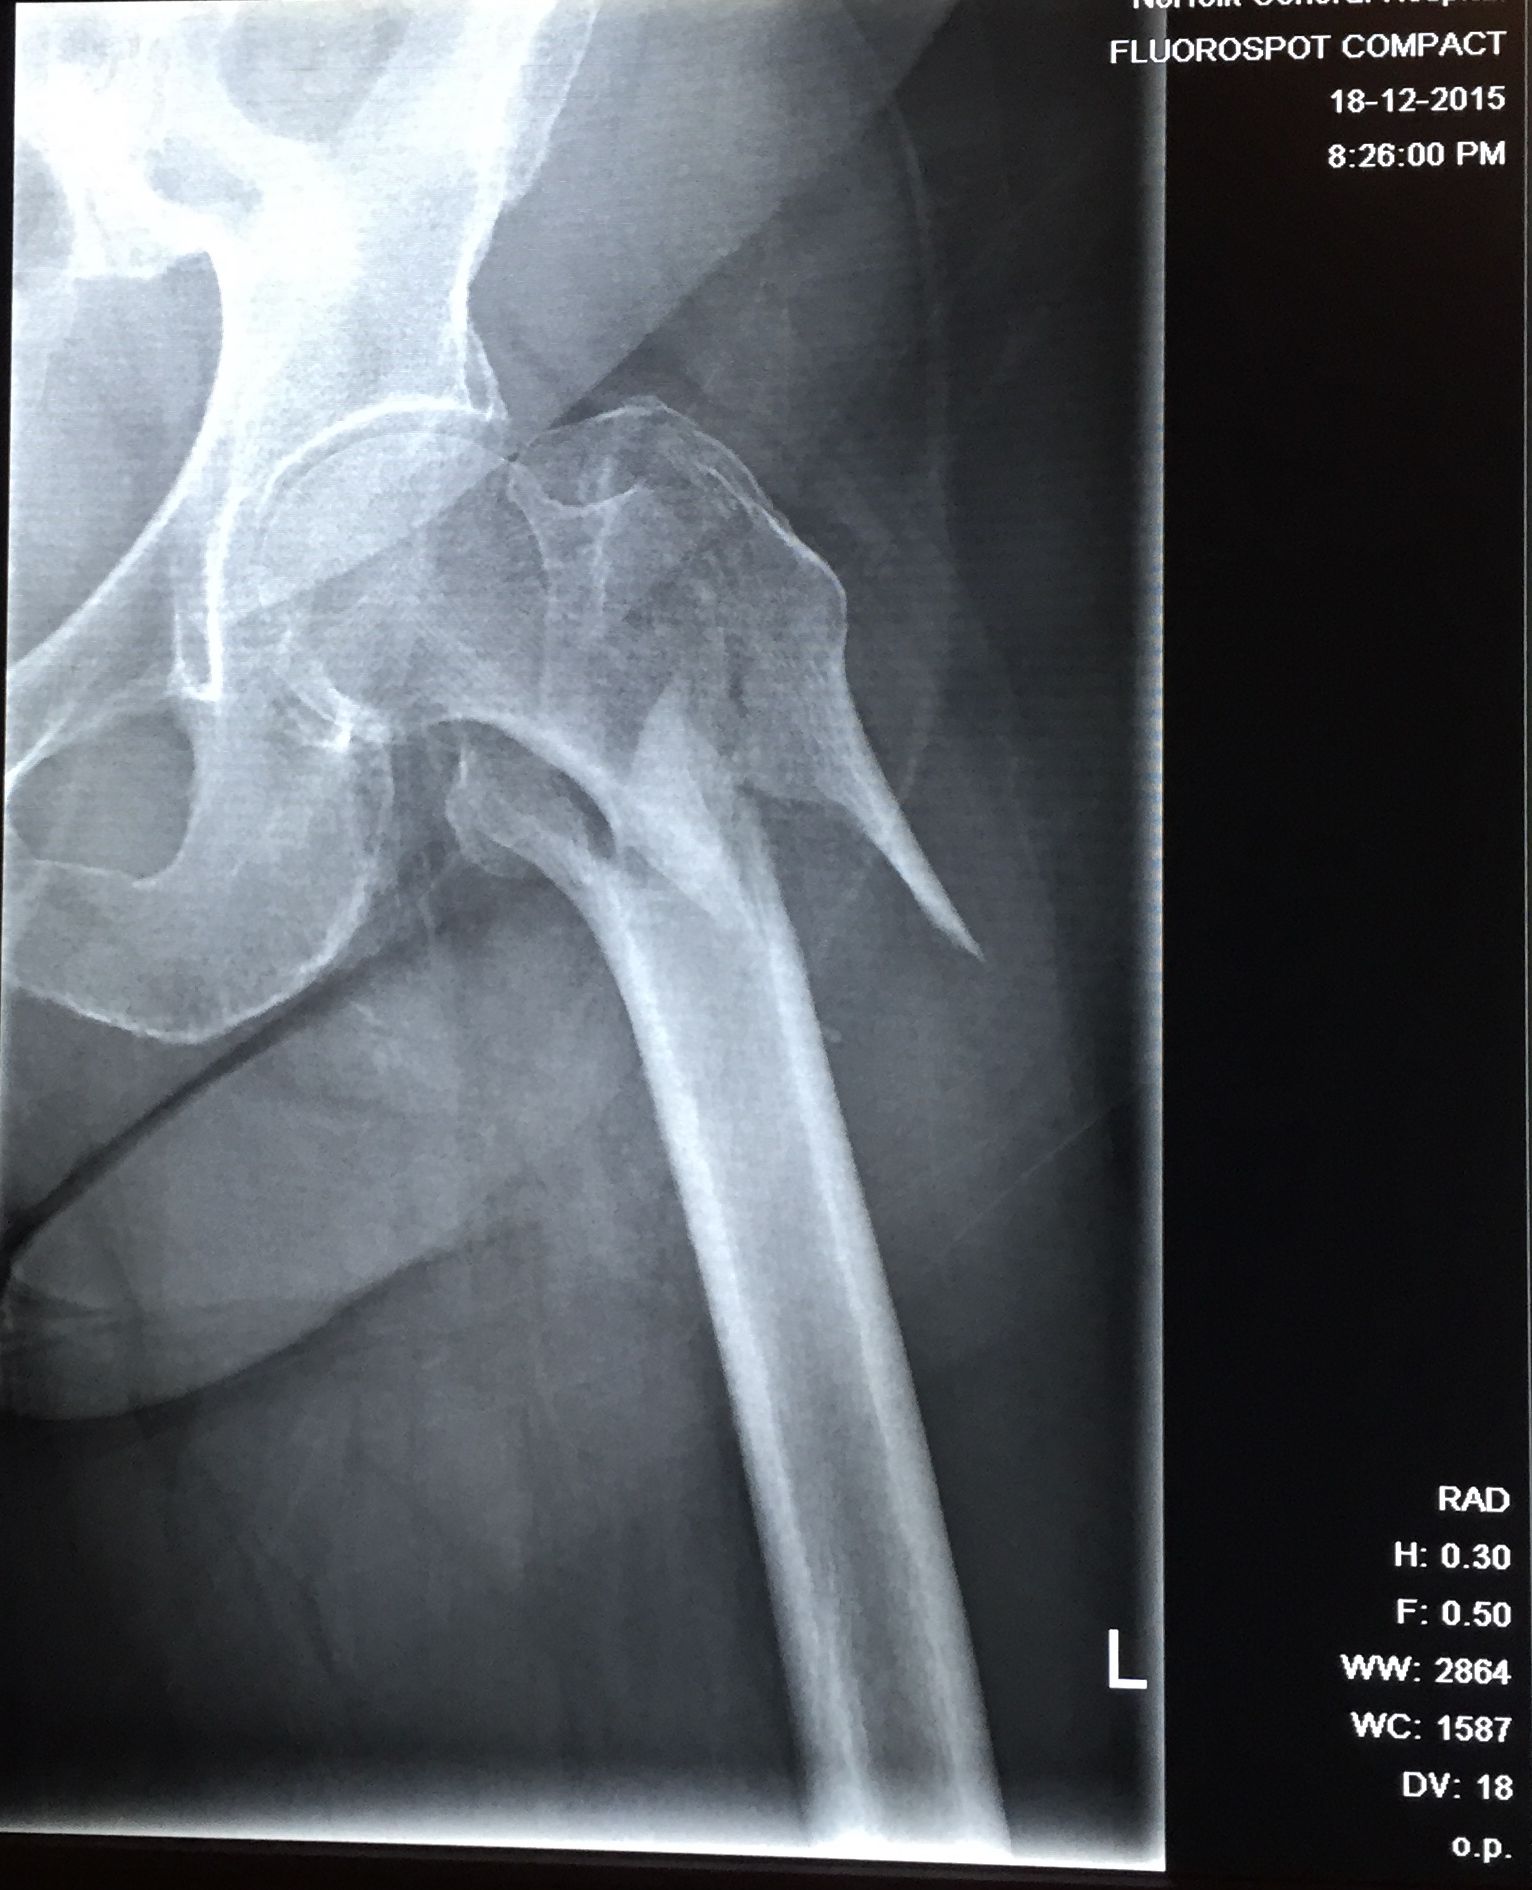

Hip Fracture X-Ray . Radiographs of the hip, radiographs of the pelvis, or radiographs of the pelvis and hips is usually. The majority of hip fractures can be diagnosed on plain film radiographs. A femoral neck fracture occurs one to two inches from the hip joint. These fractures are common among older adults and can be related to osteoporosis. The most common types of hip fractures are: This topic will review the major types of hip fractures, including basic anatomy, fracture classification, and clinical and radiographic. They tend to occur in older patients, and in those who have osteoporosis. Proximal femoral fractures are a subset of fractures that occur in the hip region. An anteroposterior view of the pelvis should be obtained along with a lateral view of the affected hip.